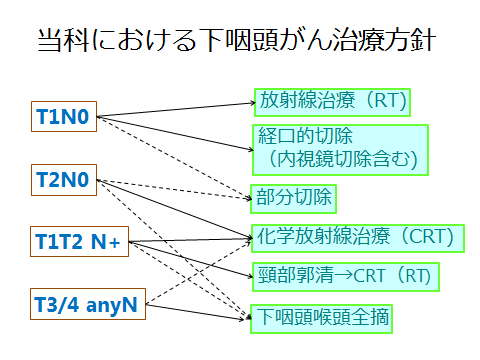

下咽頭がん 喉のつまり 痛み 熊本 くまモンファン 耳鼻咽喉科医

頭頸部癌 最近の診断 治療の進歩 耳鼻咽喉 頭頸科 順天堂医院